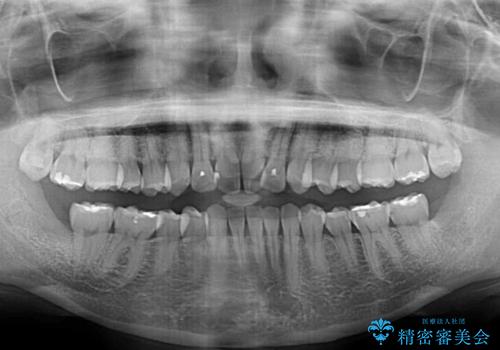

- 捻れた前歯が飛び出しており、口が閉じにくいとのことで来院された患者様です。

出っ歯というわけではないものの、前歯の捻転により口唇が押し出されている状態でした。

親知らずを抜去し、歯列全体を後方に移動させつつ、IPR(歯と歯の間を削る)でスペースを獲得し、インビザラインを用いて叢生を解消しながら前歯の突出を改善することとしました。

骨格的に上下正中がずれていたため、奥歯がしっかりと噛み合うか心配でしたが、ずれているなりに、しっかりとした咬み合わせとなりました。